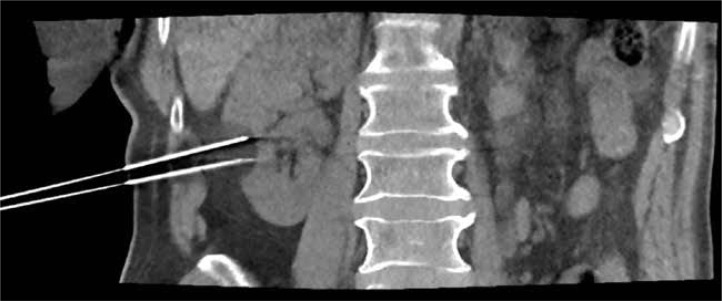

Abstract Image

Purpose: The incidence of renal cell carcinoma has been steadily increasing over the past two decades, raising the need for minimally invasive approaches. We sought to present the methodology of the percutaneous cryoablation (PCA) procedure developed based on one year of experience with 81 PCA procedures.

Material and methods: The percutaneous cryoablation programme at Wroclaw Medical University Hospital has been successfully operating for a year. During this period, patients who were ineligible for partial nephrectomy either because of numerous comorbidities or strong preference against surgery were treated with PCA. Each procedure was conducted with the close cooperation of an interventional radiologist and a urologist.

Results: Over the past year, 81 procedures in 74 individuals have been performed and thoroughly analysed. The mean and median effective radiation doses were 12.57 mSv and 10.76 mSv, respectively. Comprehensive details of our workflow are described within the body of the manuscript.

Conclusions: Percutaneous cryoablation is a technically effective treatment approach for carefully selected individuals with small renal masses. However, starting a PCA programme from scratch necessitates creation of detailed protocols, as well as close interventional radiologist and urologist cooperation. This review outlines the established workflow and shares insights gained from one year of experience with percutaneous cryoablation.